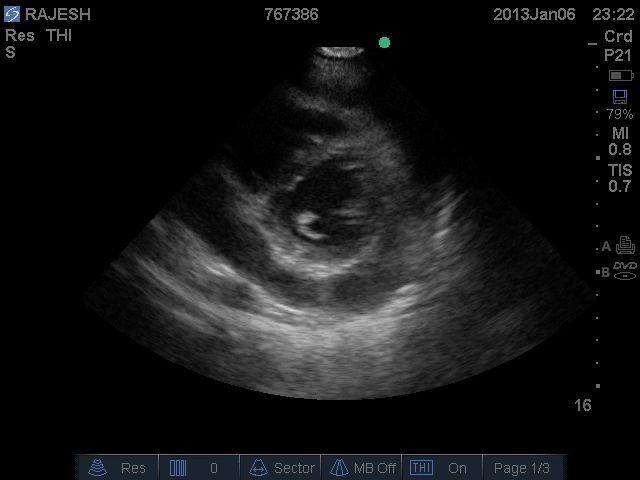

Point of Care Ultrasound :

Pericardial effusion+.

Moderate LV dysfunction

No pneumothorax.

IVC: Normal

ECHO

[on admission]: No RWMA. Valves normal

Normal biventricular function. LVEF = 55-60 %

No clots. Pericardial effusion + (2 cm in any direction)

No intra-cardiac clots. IVC dilated. Respiratory movements present